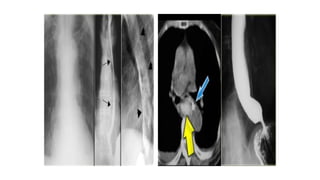

Submucosal or intramural mass.

Malignant mass at the distal esophagus.

Leiomyosarcoma of the esophagus

Esophageal obstruction due to metastatic mediastinal lymph nodes.

Malignant mass atthe distal esophagus.

Esophageal obstruction dueto metastatic mediastinal lymph nodes.